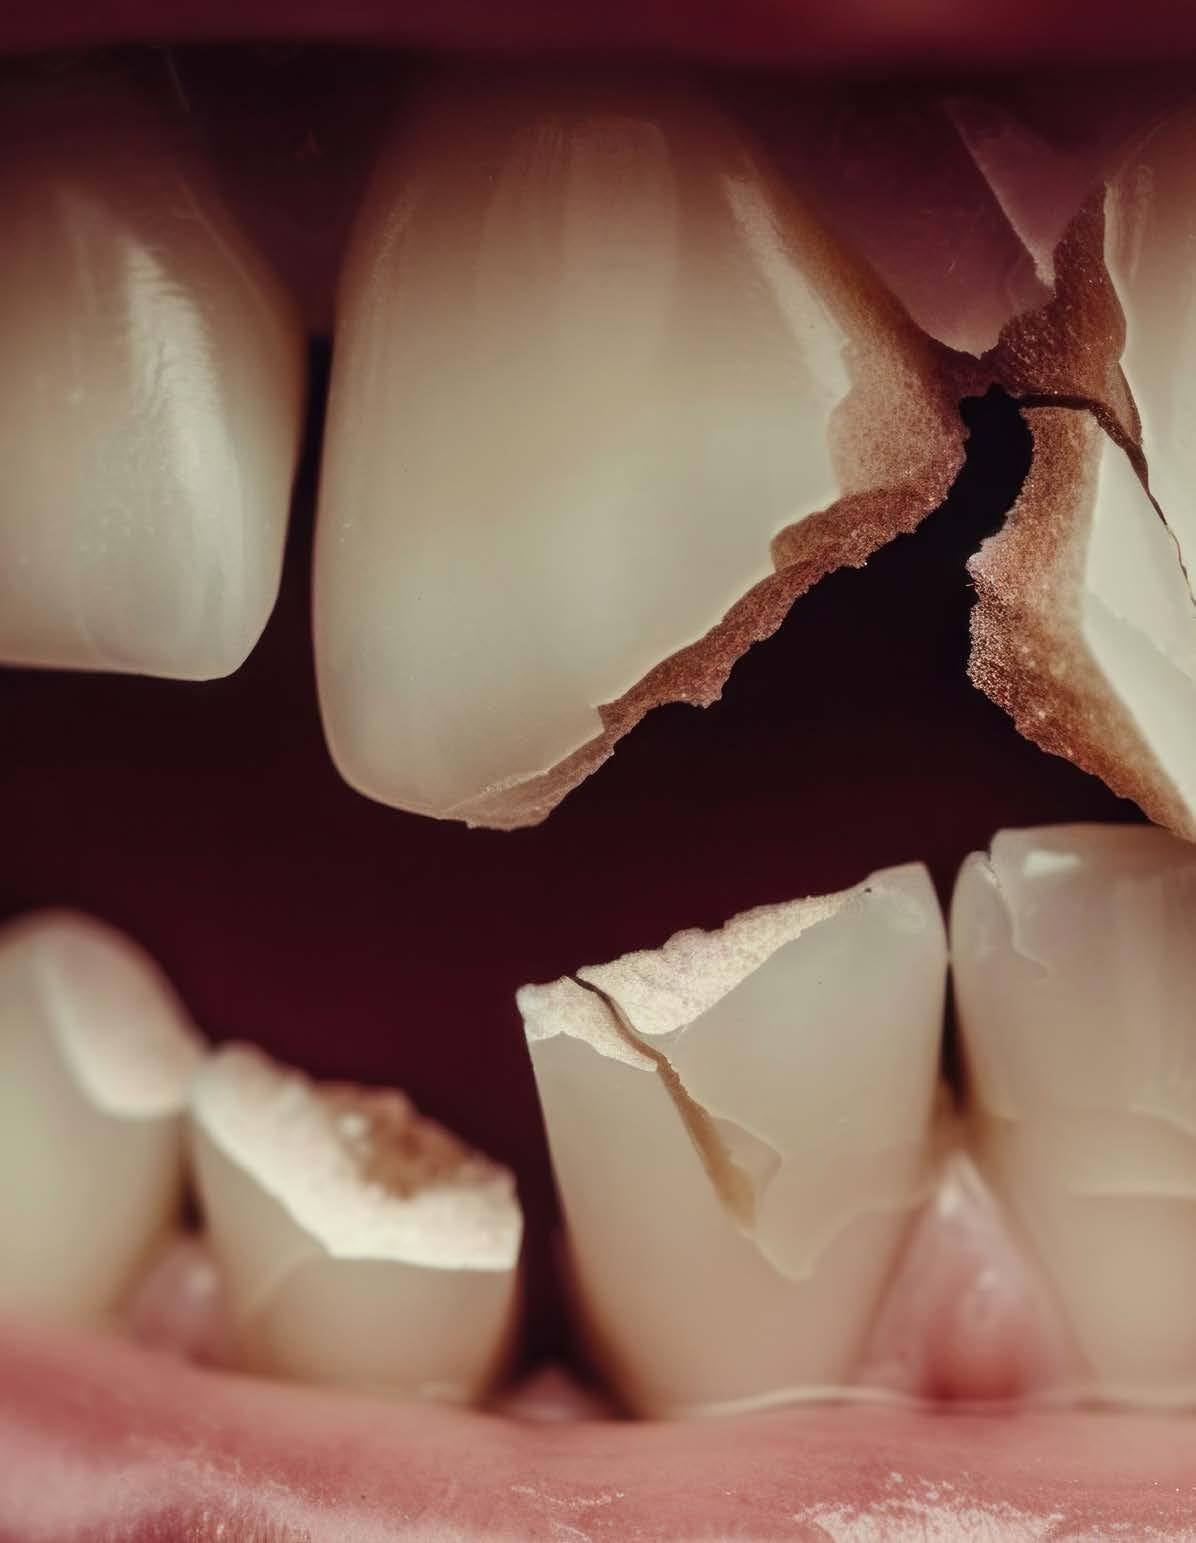

Paciente masculino de 10 años, se presenta a la consulta en la clínica Gnathos, la mamá reporta desagrado en la estética dental y facial del paciente. En la exploración clínica se observa mordida profunda, amplio número de piezas dentales con caries, fracturas dentales, mala higiene y encías inflamadas. presenta clase II división 2, se le indicaron estudios complementarios para diagnóstico asertivo, modelos de estudio,

Tratamiento de mordida profunda

radiografía panorámica y lateral de cráneo, fotografía intraoral y extraoral, historia clínica y consentimiento informado.